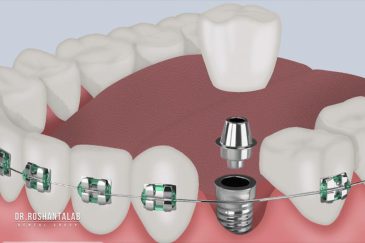

تجربه کاشت دندان دیجیتال و بدون درد در ۳ دقیقه! استفاده از برترین برندها زیر نظر جراح، با هزینه مناسب و خدمات کامل از کاشت دندان تا روکشارتودنسی دندان

برای اصلاح طرح لبخند بدون جلب توجه، از جدیدترین تکنولوژی الاینر و ارتودنسی شفاف استفاده کنید. ما تخصصیترین خدمات ارتودنسی دندان را با قیمت مناسب و شرایط اقساط ویژه ارائه میدهیم.کاشت دندان توسط بهترین متخصص ایمپلنت

انتخاب بهترین متخصص ایمپلنت که به تکنیکهای روز دنیا مسلط باشد، تضمینکننده سلامت فک و زیبایی لبخند شماست. در کلینیک دندانپزشکی دکتر روشنطلب، ما با بهرهگیری از تجهیزات دیجیتال در ۵ شعبه فعال (تهران، اصفهان، رشت و استانبول ترکیه)، خدمات تخصصی کاشت ایمپلنت دندان را برای بیمارانی که کیفیت و دقت برایشان اولویت دارد، ارائه میدهیم. در این متد، پروسه درمان با ظرافت بالا انجام شده؛ راهکاری ایدهآل برای کسانی که به دنبال درمان بدون درد با بالاترین نرخ موفقیت هستند.